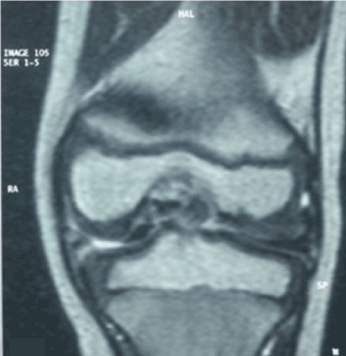

We report the case of the 5 years old boy with no significant pathological history who consulted our emergencies for a painful stiffness of the left knee following a 15 days after trauma. The child was apyretic, the knee was swollen with the presence of a patellar shock. The palpation of internal articular interlining is painful. There was a knee reducible flessum of 30 °. The standard radiography showed a discreet enlargement of the internal articular interlining (Figure 1). MRI showed a bucket handle injury of the internal meniscus (Figure 2). A partial meniscectomy under arthroscopy was performed. In peroperative we discovered an incomplete discoid medial meniscus (type II Watanabe), with presence of an extended lesion of  the medial meniscus. The patient had a resection of the dislocated part with regularization of the axial margin of the internal meniscus, thus producing an arched shape similar to the normal shape. The operative sequences were simple. The patient is asymptomatic until now at 5 years of follow-up. The functional result was excellent with complete knee mobility and normal sports activity.

Figure 2. MRI of the knee: thickening of the internal meniscus, lesion in a loose pail loop in the intercondylar incision of the knee